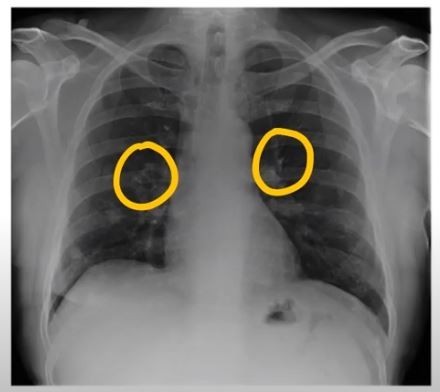

- 정기적인 건강 검진: 특히 흡연자나 가족력이 있는 경우, 저선량 흉부 CT와 같은 정밀 검진을 통해 조기에 발견해야 합니다.